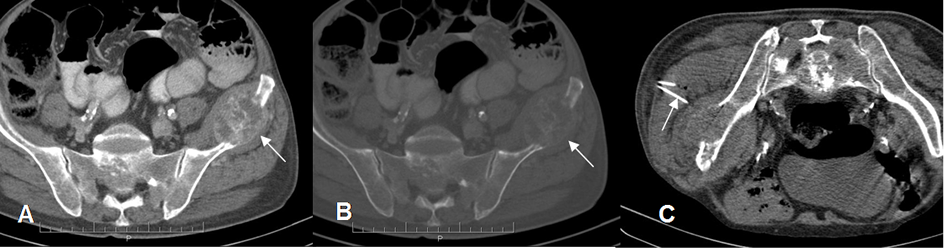

Fig 8. Guía de procedimiento con TAC.

A y B: TAC axial. Lesión lítica con masa de tejidos blandos, en el iliaco izquierdo, por metástasis de tumor broncogénico.

C: TAC axial en Prono. Toma de biopsia por vía glútea. Aguja: Flecha delgada.